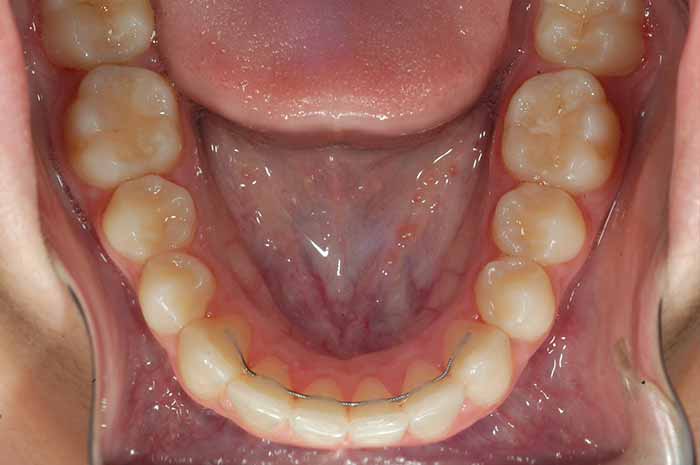

Problema:

Mordida cruzada anterior

Uno o varios incisivos superiores se situan por detrás de los inferiores, pudiendo alterar el correcto cierre de la boca.

Antes y Después